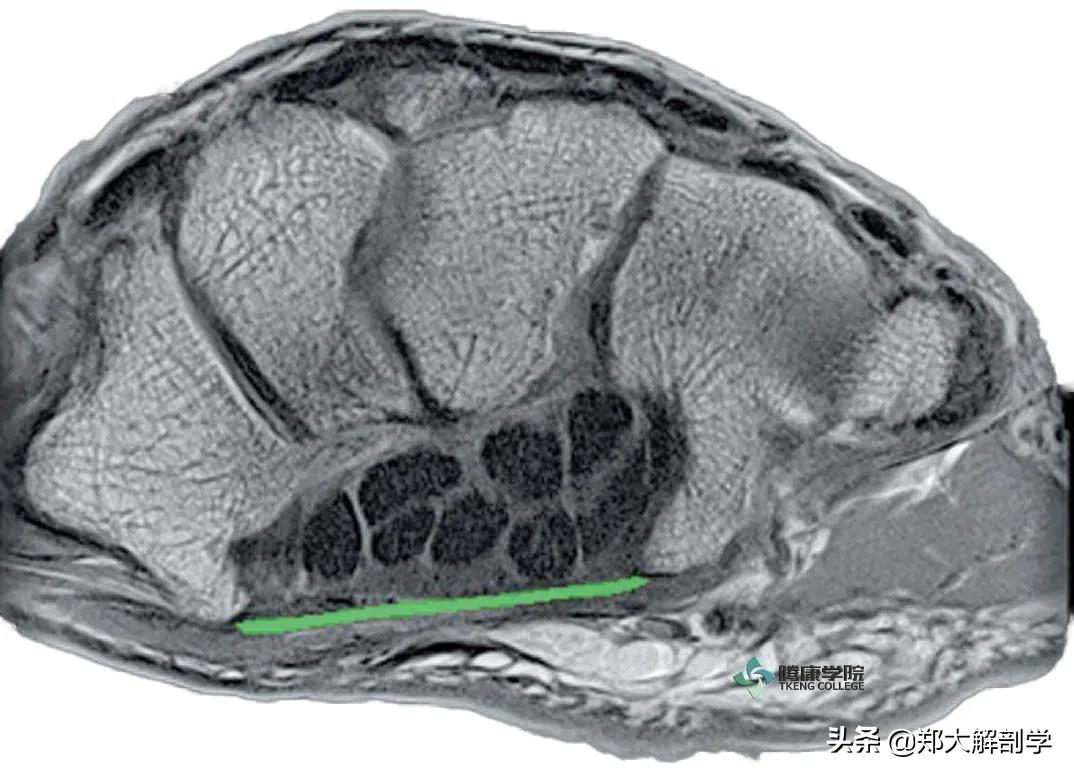

远端腕骨的MRI造影横截面,伴随着以绿色为标记的屈肌支持带

此图所显示的结构,是结合了滑动的关节软骨(白色区域)、滑液关节以及腕骨间交错连锁的强壮韧带系统

手腕中的这些紧密连接可以帮助确保腕骨的稳定度和活动度的平衡